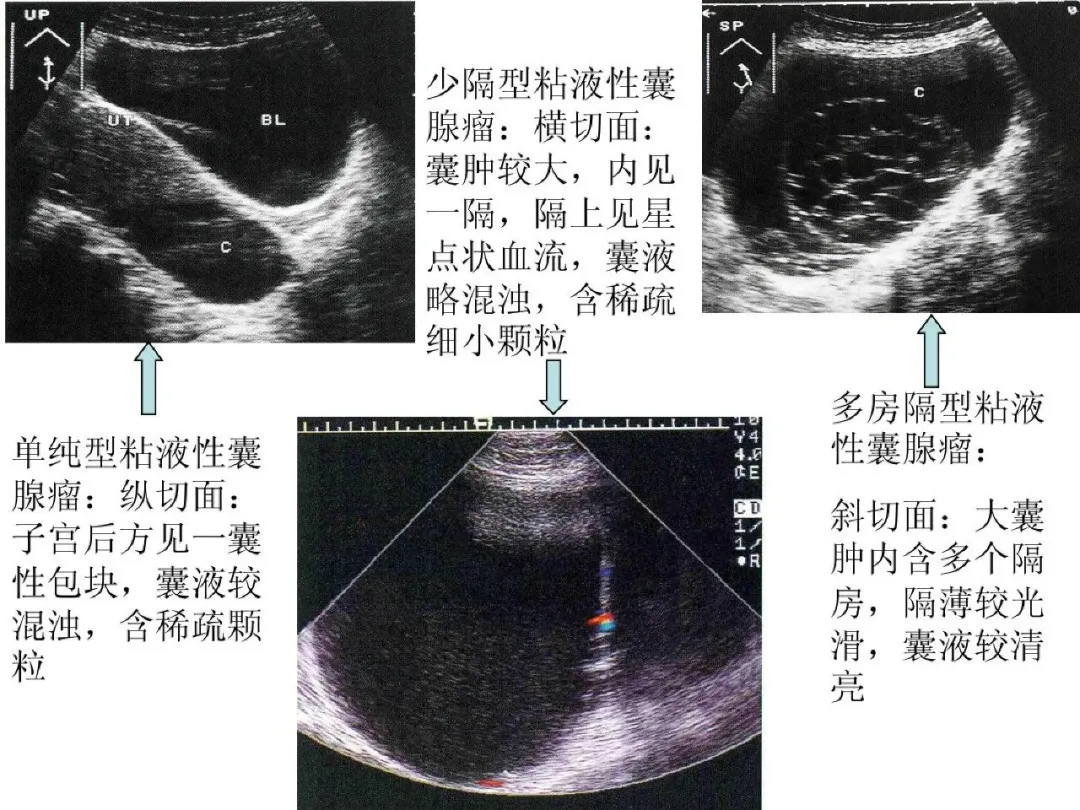

粘液性囊腺瘤

●较常见的卵巢良性肿瘤。

●二维超声图特征:大小不等,大者可达足月妊娠子宫样大小;囊壁较厚,内壁光滑;多数可见分隔,分隔或多或少,光滑,液体内显示颗粒,有的可显示梭状“胶冻体”;隔上可显示星点状血流信号。